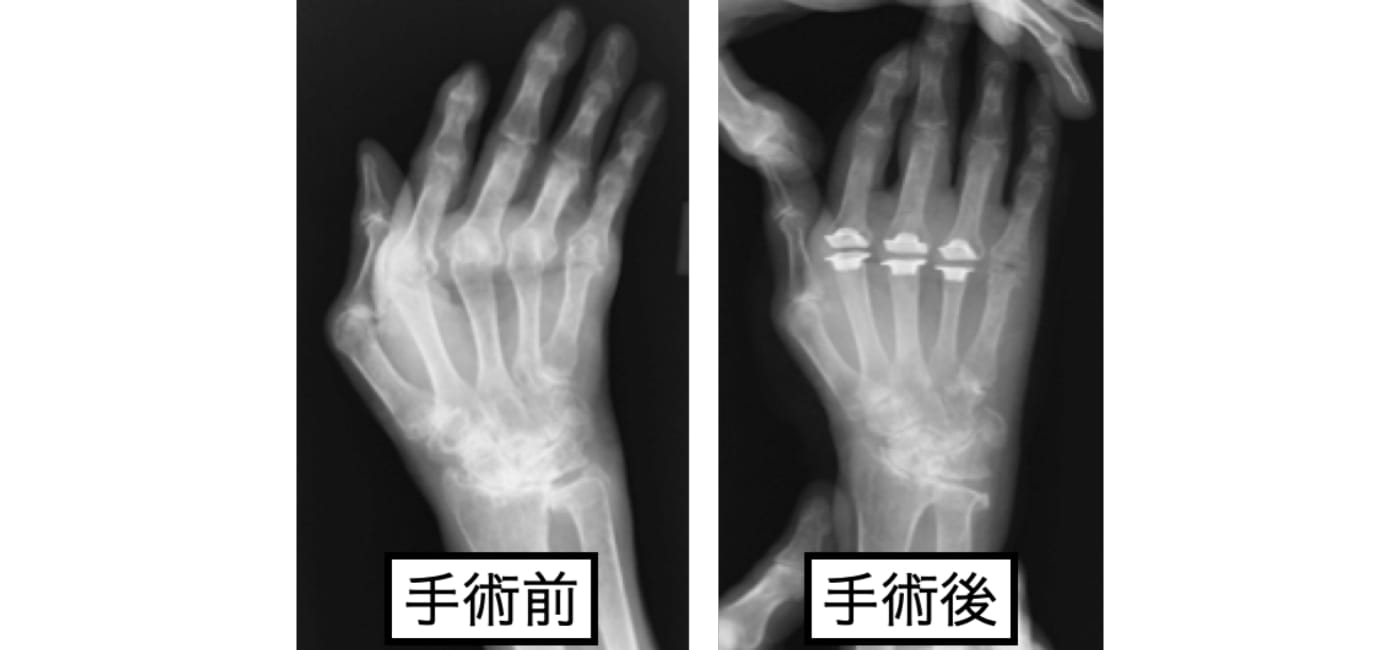

リウマチによる手部変形

リウマチによるMP関節の脱臼、尺側偏位を、シリコン人工関節を用いて手術を行った例です。

機能も大切ですが、手は一目にも触れるところです。人前に変形を気にせず、手を出せるようになりました。